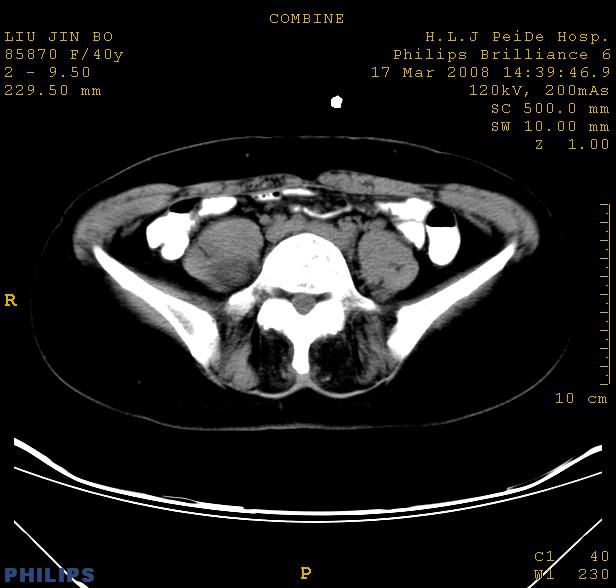

以下是引用qiuleiyu在2008-4-27 12:36:00的发言:[br]支持;右侧腰大肌后方神经源性肿瘤可能大,神经节细胞瘤?

以下是引用形影不离在2008-4-27 14:11:00的发言:[br]1.考虑右侧腰大肌脓肿。[br]2.左侧附件区炎症。[br]3.子宫增大,建议:进一步检查。